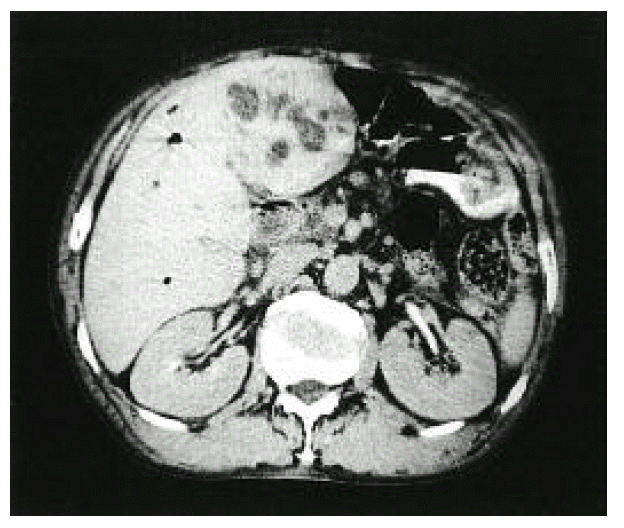

Figure 2.

Renal biopsy showing a crescent formation and a glomerulus with a cellular proliferation (H & E stain, ×200)

A 66-year-old man was admitted to Keimyung University Hospital because of decreased urine output and right upper quadrant pain. Seven years earlier, he had a Whipple’s operation for obstructive jaundice due to Ampulla of Vater cancer. At that time, the pathology report showed a moderately differentiated adenocarcinoma and biopsies of the regional lymph nodes showed no evidence of metastasis. At that time, renal function was normal and the urine contained no proteins or red cells. Two weeks before admission, the patient developed right upper quadrant dull pain, nausea, anorexia, myalgia, chills and fever. Four days prior to admission, he noticed gross hematuria, marked decrease in urine output and edema in lower extremities. On admission, his body temperature was 36.4°C and blood pressure was 110/60 mmHg. Daily urine output ranged 800–1200 mL. Face was puffy. He did not have icterus. His conjunctivae was slight anemic and revealed several petechial hemorrhages. Auscultation of the lung revealed bilateral basilar rales. No murmurs or frictions were heard. The liver was enlarged and tender. There was no splenomegaly or rash. There was marked costovertebral angle enderness. here was mild pretibial edema. Laboratory data on admission showed WBC 34,600/mm3, hemoglobin 8.3 g/dL, platelet count 95,000/mm3, BUN 16.4 mmol/L, serum creatinine 985,6 μmol/L, cholesterol 118 mg/dL, total bilirubin 3.4 mg/L, alkaline phosphatase 270 IU/L, SGPT 18 IU/L, and serum albumin 2.0 g/dL and creatinine clearance 2.5 ml/min. Urinalysis showed specific gravity 1.020, protein 2+, and urinary sediment containg two granular casts, many red blood cells and 10 white blood cells/HPF. The 24-hour urinary protein excretion was 2.4 gm and FENa was 1.7%. C3 level was 0.67 g/L (normal range: 0.8–1.2 g/L) and C4 level was 0.46 g/L (normal range: 0.2–2.5 g/L). Cryoglobulin was absent. The tests for hepatitis B and C, antinuclear antibody and rheumatoid factor were negative. Chest radiographs demonstrated bilateral perihilar pulmonary congestions. On admission, he was afebrile. He had obvious pulmonary edema as well as peripheral edema. Immediate hemodialysis resulted in a weight loss of 2 kg and respiratory improvement. Ultrasonographic examination of liver showed ill marginated cystic mass in left lobe. Computed tomography (CT) of the abdomen demonstrated 7×5cm sized multiple septated lower density lesions in medial segment of left lobe of the liver (Figure 1). Numerous blood cultures were negative. Initially the patient was treated with diuretics, albumin infusions and antibiotics (sulbactam/cefoperazone and aztreonam). On the 15th day, percutaneous needle biopsy of the kidney was performed. Light microscopy showed 17 glomeruli with two global sclerosis. The glomeruli showed endo-and extracapillary proliferation (Figure 2), with cellular crescents involving 25% of the glomeruli. The interstitium showed diffuse edema and no tubular necrosis. Immunofluorescent examination showed a diffuse granular staining with anti-IgG and anti-C3 along the capillary wall, and no staining with anti-IgM or anti-IgA (Figure 3). Needle aspiration of the liver was performed on the 19th hospital day, with the drainage of greenish pus material. Culture of the liver aspirates later grew Pseudomonas aeruginosa. Ticarcillin was given. The patient improved substantially. The levels of BUN and serum creatinine declined progressively and stabilized at 5.7 mmol/L and 176 μmol/L, respectively, by the 25th hospital day. One month after admission, the laboratory findings were : BUN 5.5 mmol/L, serum creatinine 176 μmol/L, hemoglobin 8.1g/dL. WBC 5,430/mm3 and platelet count 208,000/mm3. The 24-hour urinary protein excretion was 4.4 g/day. Follow-up CT showed almost complete resolution of previous abscess in the liver. He was discharged on the 40th hospital day with the serum creatinine level of 167 μmol/L.

Acute renal failure was the principal manifestation of renal involvement in Beaufils et al2), but proteinuria and/or hematuria also occurred in other series1112). Our patient had acute renal failure severe enough to require hemodialysis, and subsequent kidney biopsy showed endo- and extracapillary proliferation.